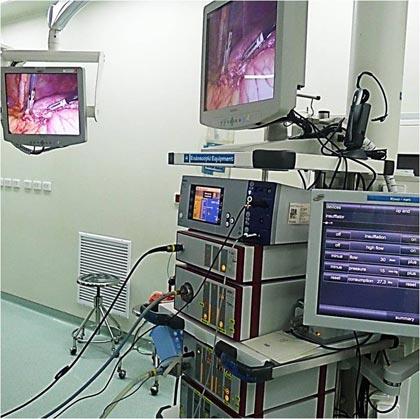

- การผ่าตัดผ่านกล้องเอนโดสโคป วิธีนี้พัฒนาขึ้นมาเพื่อแก้ไขข้อจำกัดและลดภาวะแทรกซ้อนต่างๆ ของการผ่าตัดแบบมาตรฐาน โดยศัลยแพทย์จะเจาะรูเพื่อสอดกล้องเข้าไปในร่างกาย ซึ่งเลนส์กล้องจะติดอยู่ตรงส่วนปลายของสาย ทำให้เห็นภาพพยาธิสภาพภายในได้ชัดเจน ส่วนการนำเศษหมอนรองกระดูกที่แตกออก ทำได้โดยการสอดเครื่องมือผ่านสายกล้องเข้าไป เพื่อนำเครื่องมือเข้าไปดึงหมอนรองกระดูกที่แตกออกผ่านสายกล้อง โดยไม่ต้องเจาะแผลเพิ่ม และไม่จำเป็นต้องใช้ยาสลบ ใช้แค่ยาชาเฉพาะที่เท่านั้น เพราะฉะนั้นในขณะทำผ่าตัดผู้ป่วยจะรู้สึกตัว และสามารถบอกแพทย์ได้เมื่อเกิดสิ่งผิดปกติ หรือเมื่อแพทย์นำหมอนรองกระดูกที่แตกออกมา ผู้ป่วยก็จะรู้สึกได้ทันทีว่าหายปวด ความปลอดภัยจึงมีมากขึ้น ระยะเวลาในการพักฟื้นสั้นลง นอนพักฟื้นที่โรงพยาบาลแค่ 1 คืนเท่านั้น

ความแม่นยำของวิธีเอนโดสโคป

สำหรับศัลยแพทย์ที่มีความชำนาญ วิธีนี้นับว่ามีความแม่นยำมากกว่าวิธีมาตรฐาน เพราะกล้องที่สอดเข้าไป สามารถส่องให้เห็นพยาธิสภาพภายในได้อย่างชัดเจน สามารถขยาย โฟกัสได้ สามารถมองเห็นชัดถึงเส้นประสาทนั้นๆ ช่วยหลีกเลี่ยงการบาดเจ็บต่อเส้นประสาทได้ดีกว่าการเปิดแผลปกติ ที่สำคัญไม่ต้องตัดกระดูกออก